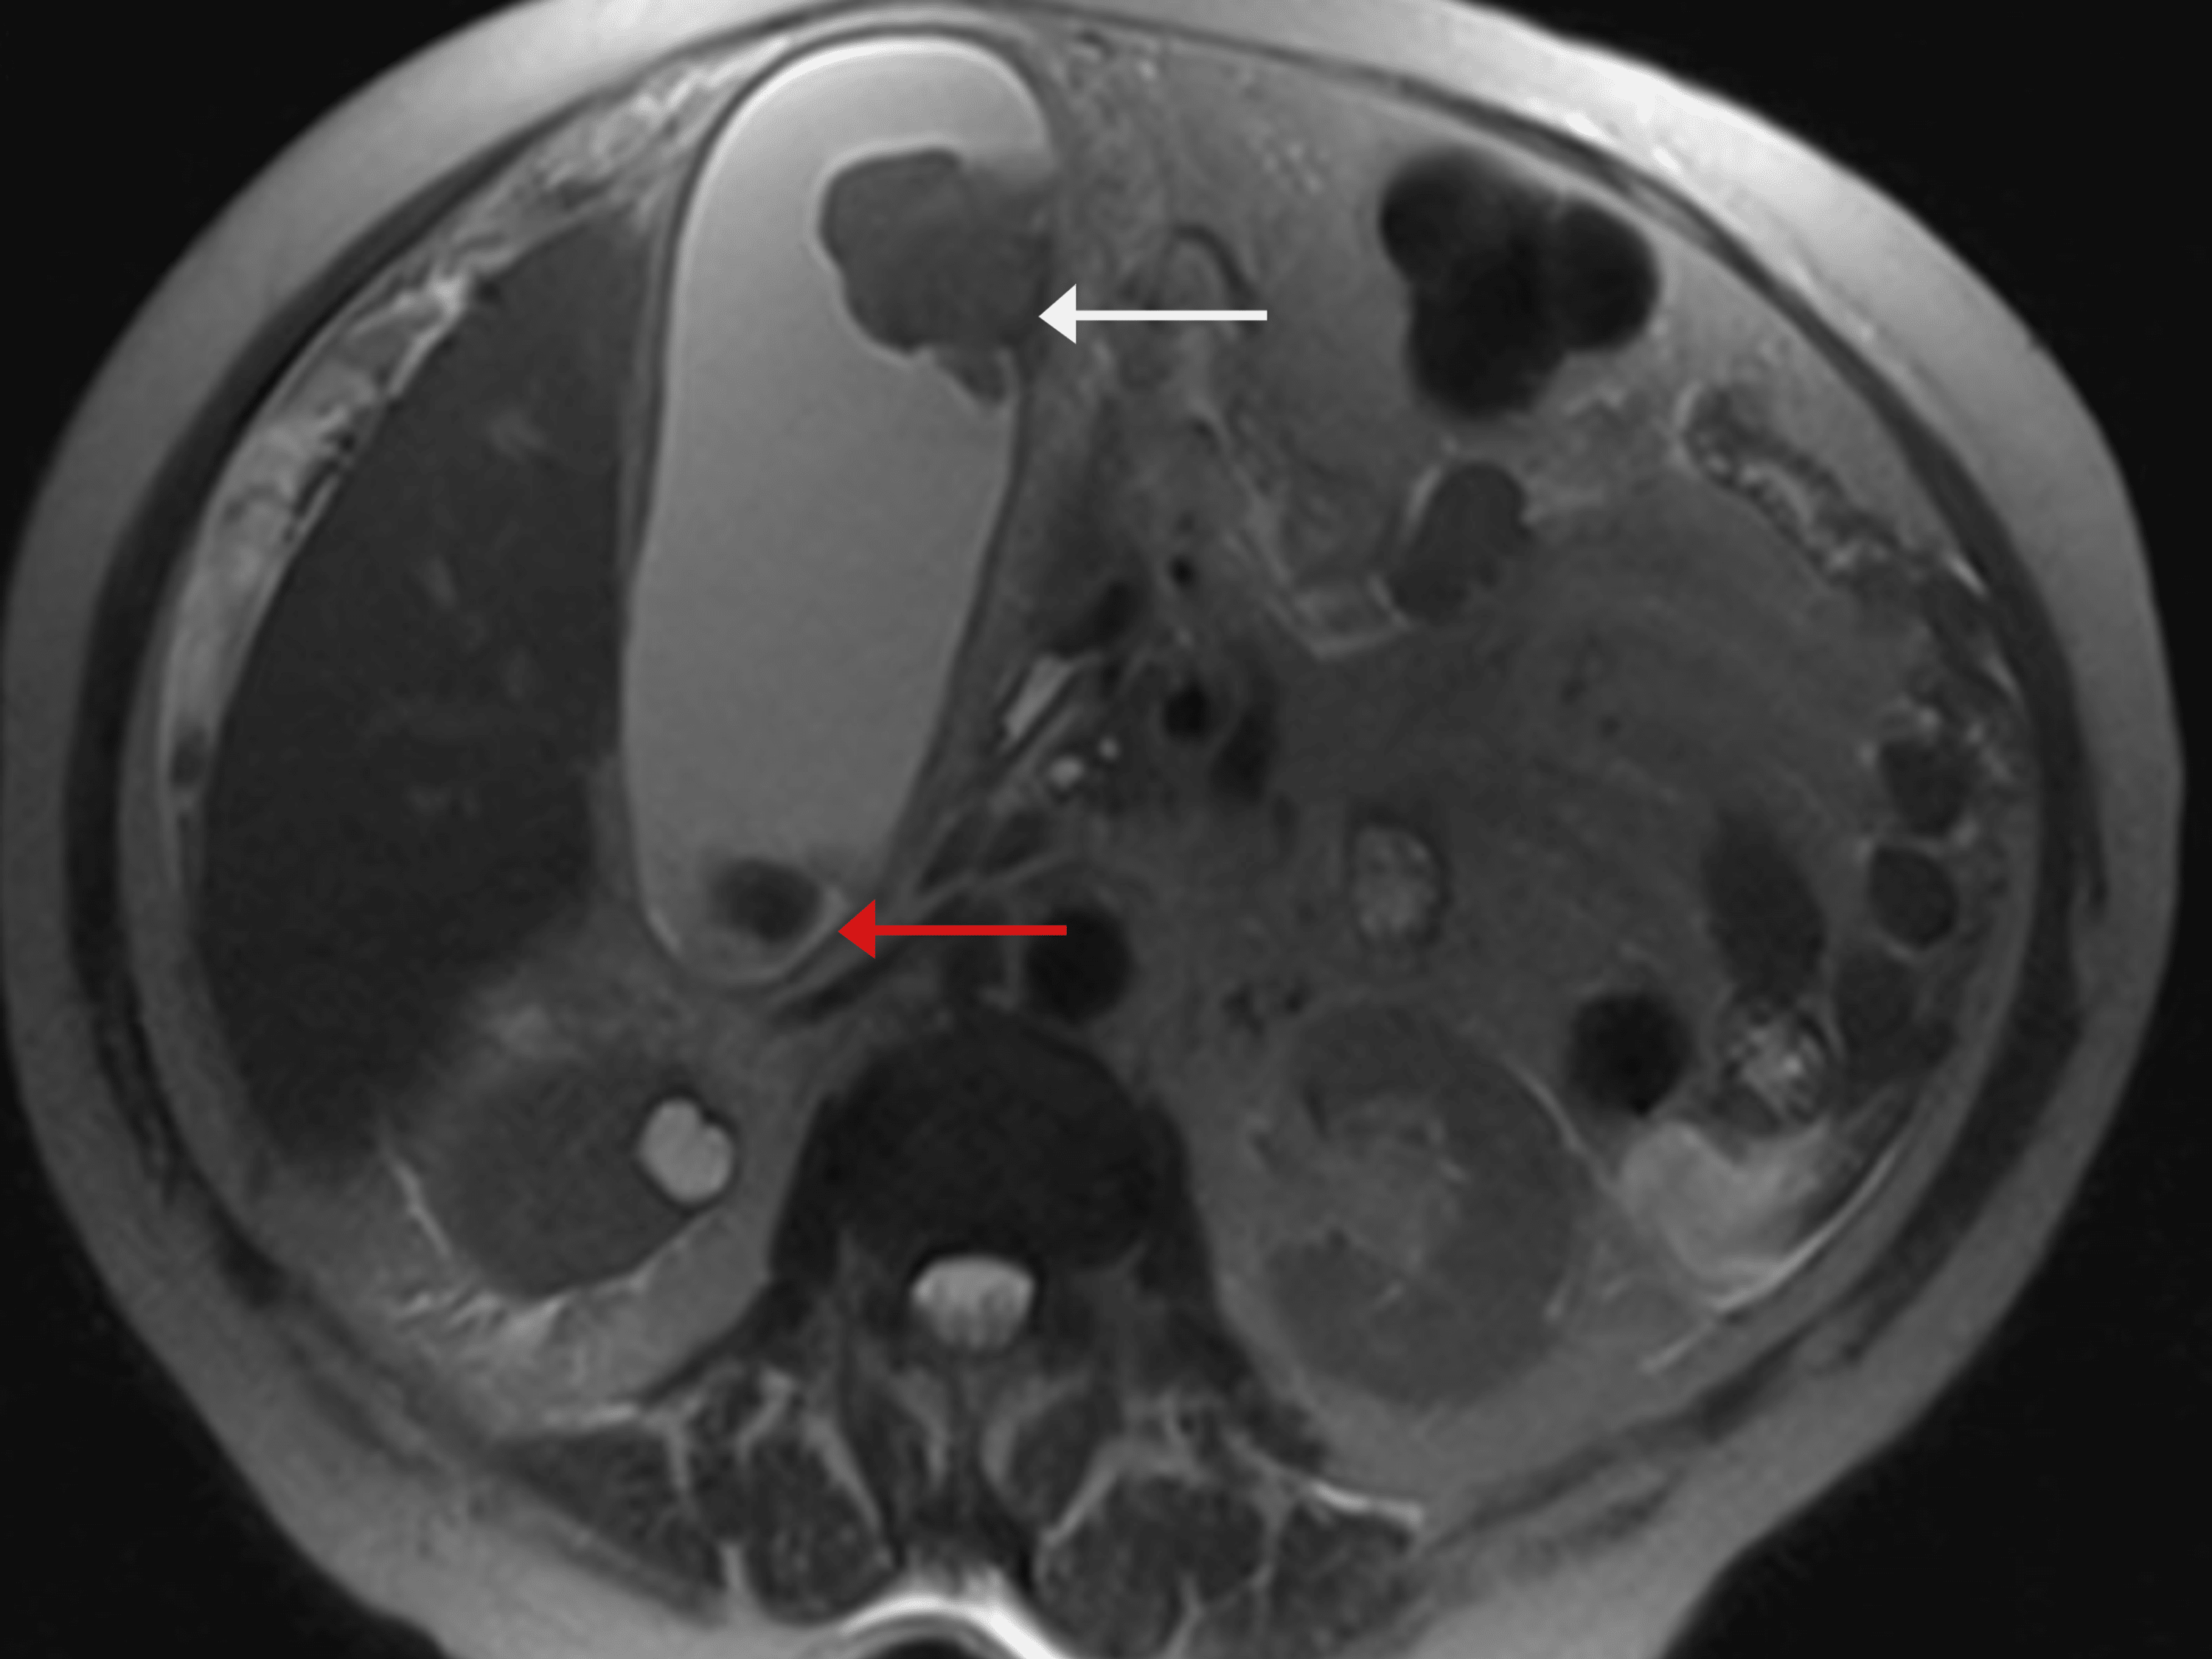

Which Gallstones Are Radiolucent . Calcified gallstones are best depicted by ct (figure (figure1c), 1c), although those with high cholesterol content are iso. But always remember about radiolucent gallstones that are. Ct of the abdomen demonstrates two radiolucencies in gallbladder (top image) and an additional lucency in the gallbladder on the lower image. Acute right upper quadrant pain and fever are very suspicious for choledocholithiasis. A type of gallstone composed primarily of calcium bilirubinate (unconjugated bilirubin and calcium). Specific names can be given to gallstones depending on their location: The presence of pneumobilia and an cholecystoduodenal fistula raises the suspicion for an ectopic gallstone as a cause of small. Gallstones (cholelithiasis) describe stone formation at any point along the biliary tree.